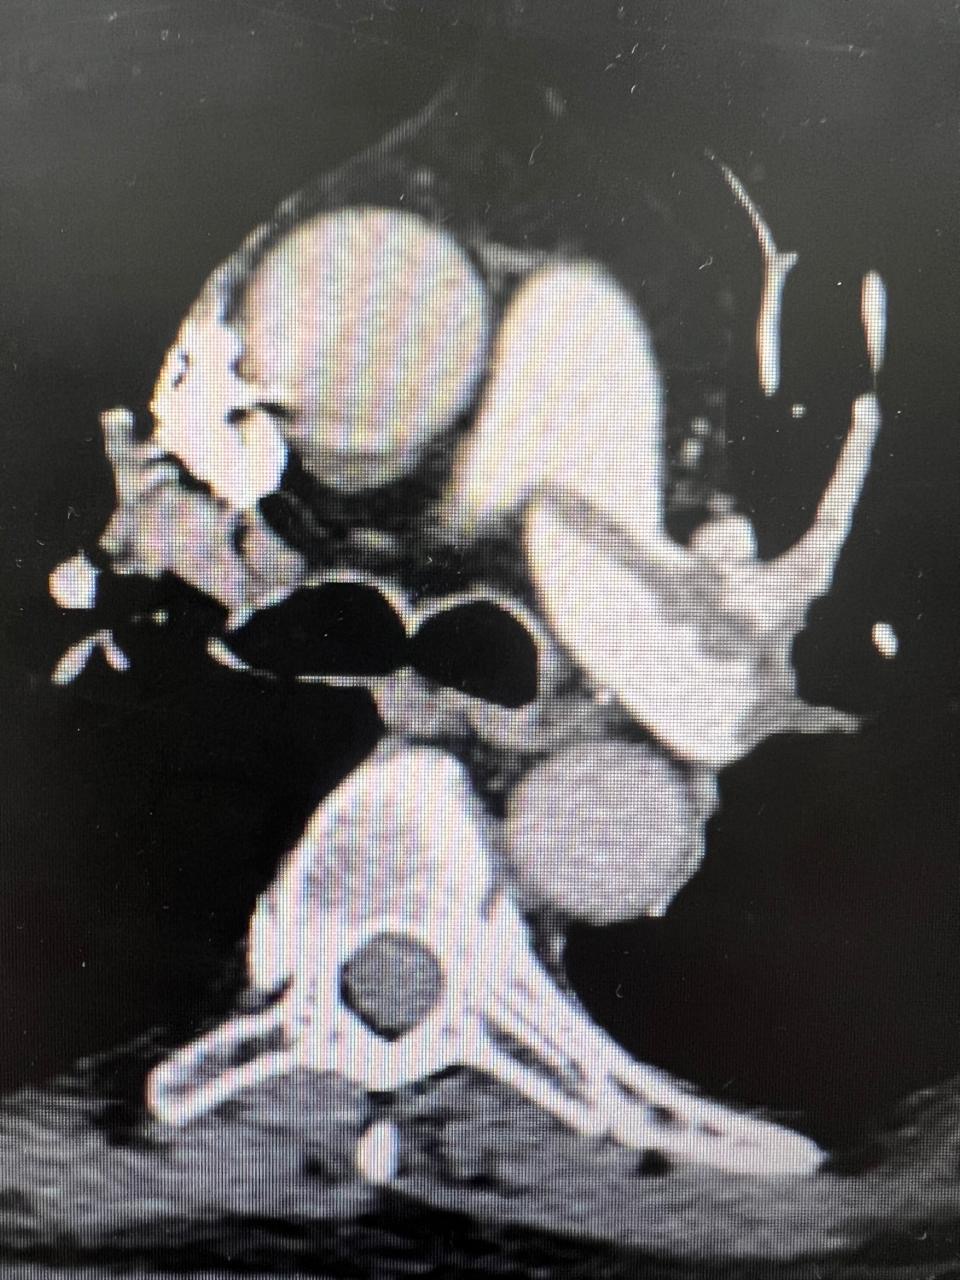

All patients were submitted to a preoperative pulmonary CT-SCAN, showing a large thrombus burden at main pulmonary arteries (figures 3 and 4).

Figure 3: CT-Scan demonstrating large thrombus burden at left pulmonary artery

Figure 4: CT-Scan demonstrating large thrombus burden at righ and left pulmonary artery